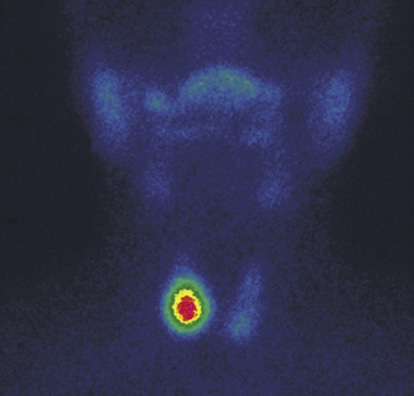

4. Fig. 4. Functional autonomy of the node of the right lobe of the thyroid gland against the background of endogenous suppression of the surrounding thyroid tissue. | |